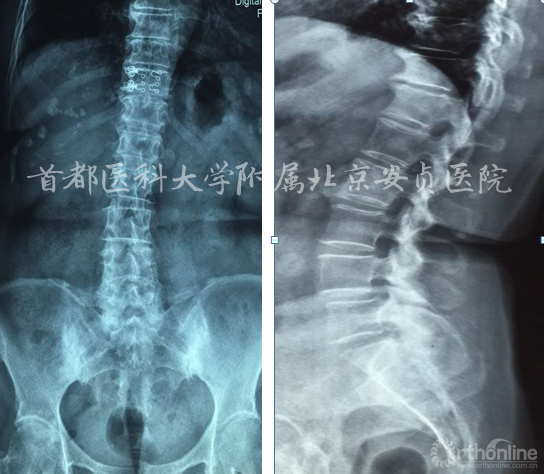

影像资料:

入院诊断:

脊髓型颈椎病、颈椎间盘突出症、腰4滑脱(l度)、腰椎管狭窄、高血压病、冠心病。

手术节段? C3/4+C5/6+C6/7

C5/6+C6/7

C5/6

C5/6 ACDF 术后2天

术后一个月

本例影像学检查结果示C3-4,C5-6及C6-7均有硬膜囊受压,但是结合症状、体征、高龄,我们选择C5-6为责任节段,进行了针对性的减压,取得了良好的效果。